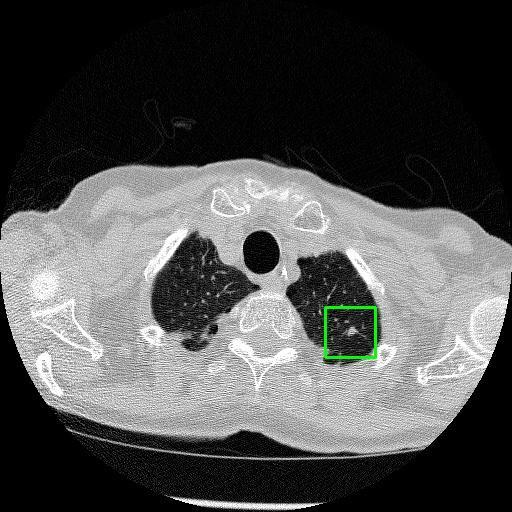

We developed an AI-based system using deep learning models for analyzing lung CT scans to detect and classify pulmonary nodules. We chose the YOLOv11 architecture for its enhanced object detection capability and adapted it specifically for medical imaging, incorporating pixel-level precision and severity classification.

Classification into three severity levels with colored bounding boxes.

Maintaining performance on small, complex features like micro-nodules tested the limits of traditional object detectors.

Successfully built and deployed an AI model (YOLOv11) capable of detecting lung nodules in CT scans with high accuracy and real-time performance.

Designed a severity classification system that categorizes nodules into null, moderate, and severe using colored bounding boxes, assisting in rapid clinical decision-making.